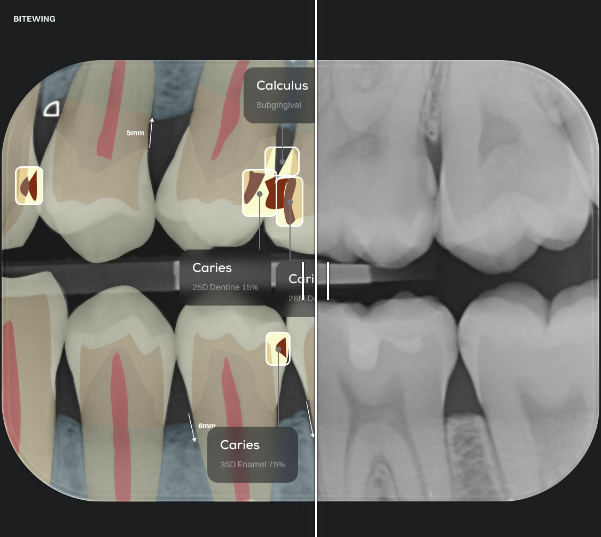

Dental procedures produce a huge amount of data- from detailed X-rays to patient records and clinical notes. To make sense of it all, more and more professionals are turning to AI. These smart systems are trained on thousands of annotated dental images and real-world clinical data, learning to recognize patterns and spot abnormalities-often before we can.

AI is not here to replace dentists, it gives them a powerful assist to be more consistent in their opinions. Take Pearl AI’s Second Opinion, for instance- it’s FDA-cleared and used by dentists to double-check their findings, especially for catching early caries or subtle radiolucency that might otherwise go unnoticed.

Another powerful player is Overjet, which offers tools for detecting decay, measuring bone levels, identifying margins, and even assisting in implant planning. With AI like this in the chairside toolkit, dentists can diagnose earlier, explain better, and treat smarter.